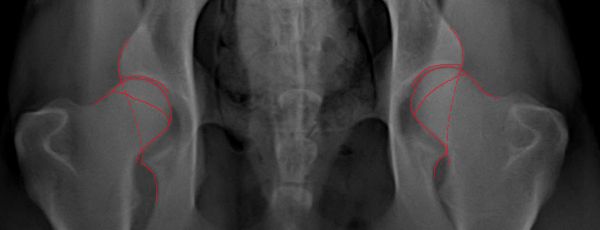

OFA: good!!! Congrats, they should definitely pass!!

This is what I see, maybe its wishful thinking.

IMO good to excellent.

His legs are not parallel, how does this make the 2 sides look different?

Um I think they are pretty fantastic! I've sent in much worse positioning and not as good of hips and passed just fine.

Doesn't matter on this dog, it's not a close call. He clearly has normal hips for breed and age.

I am most likely wrong, but I think I can see transitional vertebra......anyone else see that?....